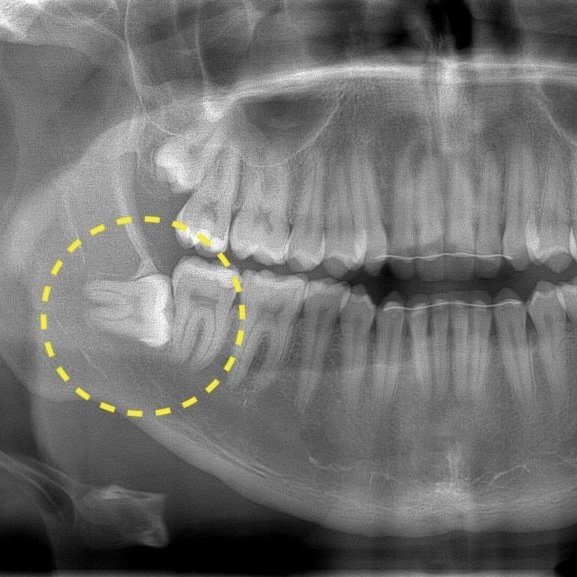

Хірургічне видалення зуба мудрості у Львові можливе лише в клініці, де є стоматолог з відповідною кваліфікацією. Не рекомендуємо шукати видалення 8 зуба за доступною ціною, бо найважливіше – це компетенція та професіоналізм лікаря і репутація клініки. Підготовка до хірургічного видалення зуба обов’язково включає рентген та/або комп’ютерну томографію, щоб оцінити ситуацію та вибрати оптимальний метод видалення 8 зуба. Перед видаленням пацієнтам проводять професійну гігієну щоб усунути скупчення бактерій з ротової порожнини для мінімізації ризику запалення та прискорення загоєння після екстракції.

До складного видалення зуба мудрості вдаються в основному на нижній щелепі, оскільки кісткова тканина щелепи тут більш масивна і щільна. Крім того, нижні зуби більші і часто мають розгалужену кореневу систему.

Видалення ретинованого зуба мудрості це складне видалення . Ціна при цьому вища і залежить від технічної складності операції по видаленню зуба.